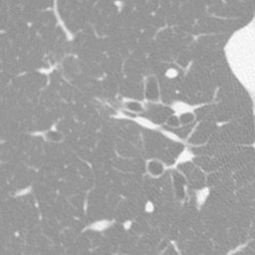

Channel 1. Original Image